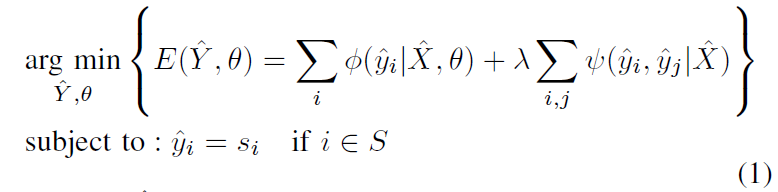

最小化目标函数:

一看到最小化能量函数,就往概率图模型方向靠了,实际上图像分割的一大分支就是概率图模型。

- X ^ \hat X X^ 为用户提供的 bbox 内的 sub-image(论文是这么说的),实际上就是一个 bbox 里的内容,它作为了全局观测,来计算第一项条件概率【这些概念来自CRF,可以搜相关论文看看】

- Y ^ \hat Y Y^ 为 X ^ \hat X X^ 的 target label,更贴切一点说应该是 X ^ \hat X X^ 中各个像素的预测 label 组成的一种 “分配方案”,此时的 Y ^ \hat Y Y^ 是根据用户给的 bbox 自动分割出的结果

- 一元项 ϕ \phi ϕ 也叫一致性项,可以看作是给第 i i i 个像素分配的标签为 y ^ i \hat y_i y^i 的概率(属于前景还是背景)

- 二元项 ψ \psi ψ 衡量了两个像素 i i i 和 j j j 之间的差异

- λ \lambda λ 为二元项的权重,也就是希望二元项对目标函数的影响有多大

对能量函数的优化方法类似于 DeepCut 中弱监督的学习方法,但是在 DeepCut 中能量函数是基于训练集中所有图像的概率和 label map 进行优化的,而在本文是基于单个 test image 进行优化。

此时就可以将优化目标函数(1)分解为两步,一是 label update step,二是 network update step:

(1)label update step

θ 固定,这样优化目标(1)简化成 CRF 问题:

为方便实现,将等式(5)转换为无约束优化等式: